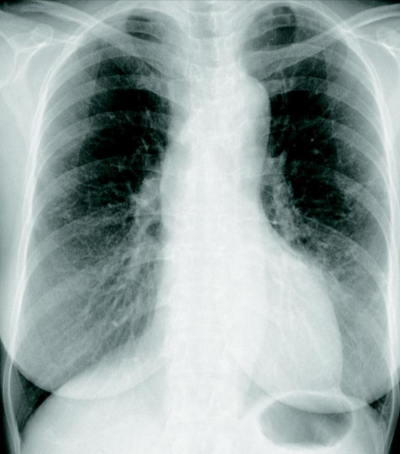

60歳の女性。咳嗽を主訴に来院した。5年前から関節リウマチに対し、副腎皮質ステロイドとメトトレキサートの内服処方を受け、病状は安定している。1か月前から咳嗽が続いている。

胸部エックス線写真及び胸部CTを別に示す。気管支鏡検査を行い、気管支洗浄液の抗酸菌検査で塗抹陽性で、非結核性抗酸菌が培養された。血液検査で抗MAC〈Mycobacterium avium complex〉抗体が陽性であった。